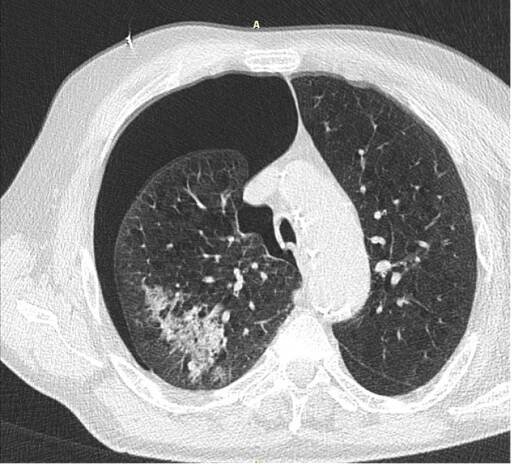

Pneumotorax (PNO) je definován jako nahromadění vzduchu či jiného plynu v pleurální dutině. Pleurální dutina je uzavřený prostor obklopující plíce, je ohraničený nástěnnou a plicní pleurou a je v něm podtlak.

Při pneumotoraxu se vzduch dostává do pleurální dutiny, což je mezera mezi plícemi a hrudní stěnou (přesněji mezi poplicnicí a parietální pleurou). Následkem ...